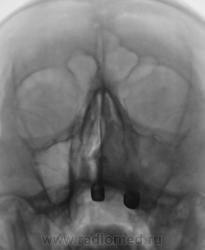

А меня очень "впечатляет" потеря структурности внутренней стенки левой гайморовой полости и как бы продолжение тени на левую носовую полость. Гайморит гайморитом, а исключть заболевание не мешает, позавчера такой примерно "фрукт" приходил от невропатолога с диагнозом - "что то под глазом вылезло", а клинически уже "одеревенение" верхней челюсти...

Тут разве нет диструкции наружной и внутренней стенок левой гайморовой пазухи?

Пациент ощущает "шишку" со стороны полости носа. Беспокоят головные боли.

Скорее всего - онкология.

Вроде бы и ДА, а вроде бы и НЕТ...какое то двойственное впечатление: есть нечеткость наружной стенки на первом среже, есть связь с носовым ходом на всех трех, есть небольшое увеличение пазухи на третьем....а в целом....все таки больше ЗА, чем против...